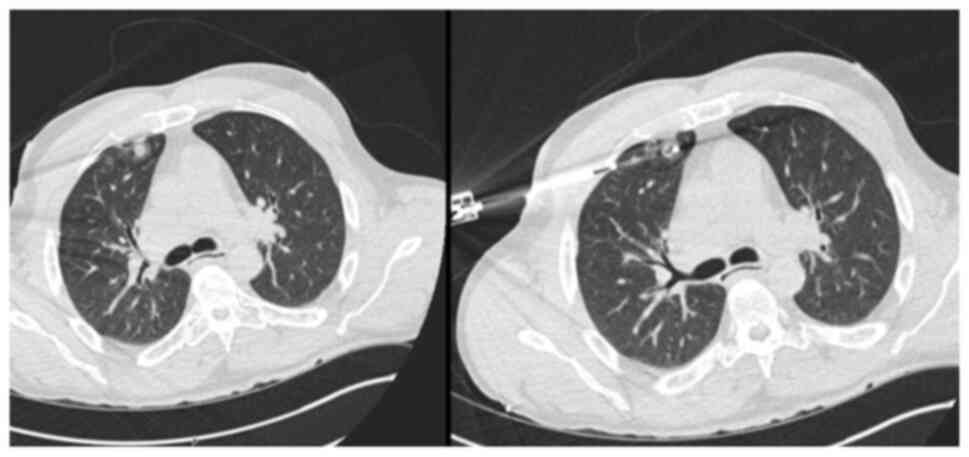

A 52-year-old male patient was diagnosed with PSC in 2015 at King s College Hospital (London, UK), confirmed by liver biopsy. He remained under regular surveillance by the hepatology team until April, 2017, when he presented with new-onset obstructive jaundice. Contrast-enhanced computed tomography (CT) revealed a hilar mass causing bilateral biliary dilation, and the working diagnosis was that of hCCA. After staging with fluorodeoxyglucose positron emission tomography (FDG-PET) and diagnostic laparoscopy, no evidence of metastatic disease was identified (Fig. 1). Portal vein embolization was performed to induce hypertrophy of the future liver remnant (FLR) in preparation for an extended right hepatectomy (ERH). Given the background of PSC, a 10-week interval was observed before repeat imaging, which demonstrated marginal FLR growth. The future liver remnant-to-body weight ratio (FLRBWR) was 0.42 at the time of surgery, corresponding to ~20% of total liver volume (Fig. 2).

Axial computed tomography image (left

panel) demonstrating bilateral intrahepatic biliary dilatation

secondary to a hilar cholangiocarcinoma (yellow arrow). Coronal

fluorodeoxyglucose positron emission tomography image (right panel)

illustrating intense metabolic activity at the liver hilum

corresponding to the hilar mass (yellow arrow). The image was

obtained in May, 2017.

Figure 1

Axial computed tomography image (left panel) demonstrating bilateral intrahepatic biliary dilatation secondary to a hilar cholangiocarcinoma (yellow arrow). Coronal fluorodeoxyglucose positron emission tomography image (right panel) illustrating intense metabolic activity at the liver hilum corresponding to the hilar mass (yellow arrow). The image was obtained in May, 2017.